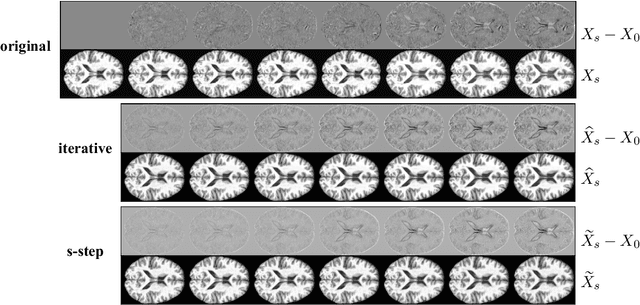

Abstract:This paper focuses on the analysis of sequential image data, particularly brain imaging data such as MRI, fMRI, CT, with the motivation of understanding the brain aging process and neurodegenerative diseases. To achieve this goal, we investigate image generation in a time series context. Specifically, we formulate a min-max problem derived from the $f$-divergence between neighboring pairs to learn a time series generator in a nonparametric manner. The generator enables us to generate future images by transforming prior lag-k observations and a random vector from a reference distribution. With a deep neural network learned generator, we prove that the joint distribution of the generated sequence converges to the latent truth under a Markov and a conditional invariance condition. Furthermore, we extend our generation mechanism to a panel data scenario to accommodate multiple samples. The effectiveness of our mechanism is evaluated by generating real brain MRI sequences from the Alzheimer's Disease Neuroimaging Initiative. These generated image sequences can be used as data augmentation to enhance the performance of further downstream tasks, such as Alzheimer's disease detection.